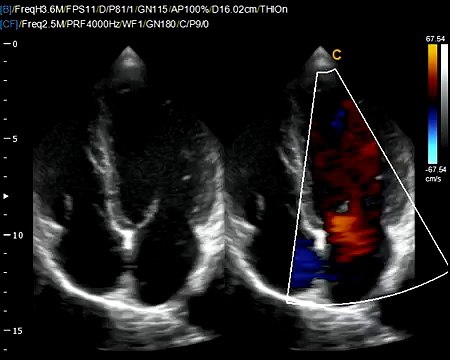

Example of volumetric probe scan with 4D Virtual HD ultrasound. Virtual HD is a breakthrough in real-time 4D technology. For more information on the low cost color doppler ultrasound Chison Q5, and Chison Q9 visit: keebomed.com/collections/color-doppler-ultrasounds